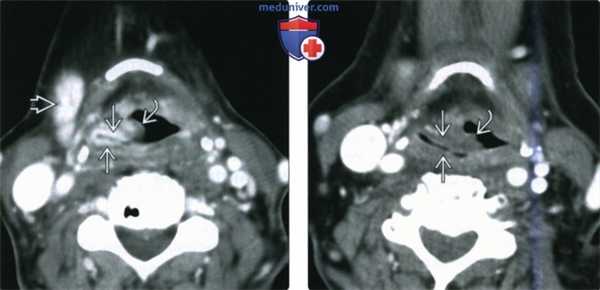

(Слева) КТ с КУ, плоскоклеточный рак надсвязочного отдела гортани слева, ранний период после лучевой терапии. Выраженное накопление контраста в слизистой оболочке правого грушевидного синуса и утолщение черпалонадгортанной складки. Обратите внимание на выраженное накопление контраста в правой поднижнечелюстной слюнной железе, что является ожидаемым эффектом радиации.

(Справа) Этот же пациент три года спустя. Контраст в слизистой оболочке больше не накапливается, то черпалонадгортанная складка остается утолщенной. Утолщение структур надскладочного отдела гортани достаточно часто встречается у пациентов, перенесших курс лучевой терапии.